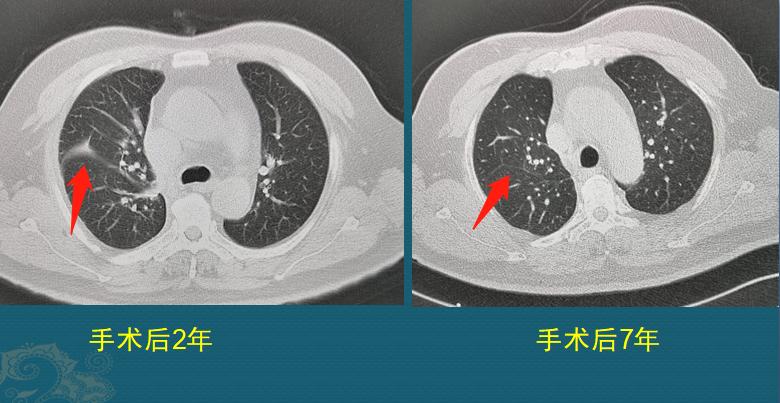

为了降低复发风险,他在手术后又做了局部放疗、全身化疗和细胞免疫治疗,至今已经7年多了,多次复查恢复很好:

左图是手术后第2年,手术区有一点胸膜肥厚,这个是正常反应,对肺功能没有影响;右图是术后第7年复查,胸膜肥厚也恢复了。